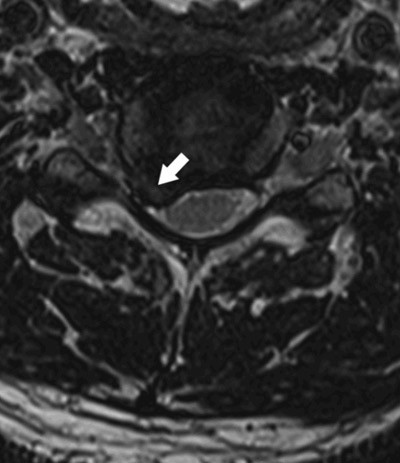

Hos pasienter med smerter lavt i ryggen med utstråling er det rapportert en prevalens av lumbale skiveprolapser på 65 %, mens prevalensen ved smerter uten utstråling var 57 % (16). Imidlertid finner man også lumbale prolapser hos 25 % i en normalpopulasjon (15). Også i cervikalcolumna har skivebukinger og prolapser en høy prevalens hos asymptomatiske, den er over 50 % i aldersgruppen over 64 år (17). Det å ha skiveprolaps er altså ikke ensbetydende med å ha symptomer.

Prolapser som disloserer eller komprimerer nerverøtter er imidlertid sjeldent hos symptomfrie (15, 18) (fig 3). Finner man denne typen prolaps kombinert med symptomer som passer med den aktuelle nerverot, vil man ha etablert en sannsynlig årsakssammenheng. Prolapser er ikke stabile strukturer. Særlig de som har en smal basis mot skiven viser stor tendens til resorpsjon. Under konservativ behandling vil en tredel skrumpe i løpet av de første seks uker og to tredeler i løpet av seks måneder (13). Funn av skiveprolaps er altså i seg selv ikke indikasjon for kirurgisk behandling. Som alltid er det kliniske bildet avgjørende.